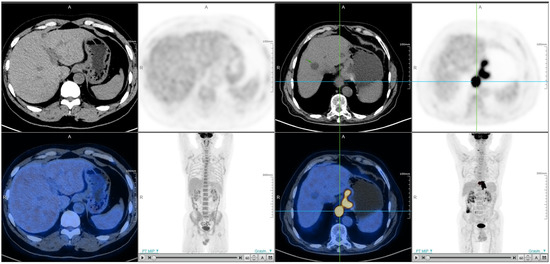

2. Materials and Methods

3.1. GLUT-1 Protein Expression in Patients with Different Levels of SUVmax